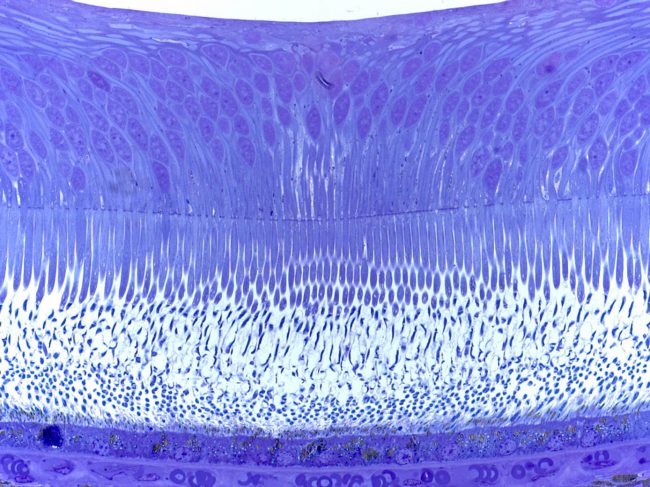

- Photoreceptor toxicity assessment

- Retinal Pigment Epithelium (RPE) toxicity assessment

- Photoreceptor toxicity assessment

- Retinal Pigment Epithelium (RPE) toxicity assessment